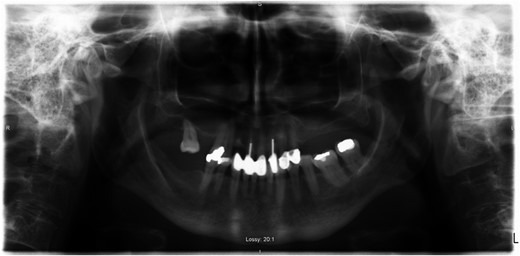

A 69-year-old female with a history of bilateral total hip replacements presented with rigors, fever and sudden onset left groin pain. A pelvic X-ray showed well-fixed implants. Blood results revealed a leucocytosis (white cell count 22.3 × 109 l–1) and elevated C-reactive protein (211 mg/l). Ultrasound-guided aspiration of her left hip grew Streptococcus gordonii. No source infection could be identified apart from a new chronic sinus infection in a left upper incisor. Following a discussion with the patient a 6-week course of intravenous ceftriaxone was started and was successful in normalizing her inflammatory markers. She was placed on long-term suppressive amoxicillin following this. Her suppressive antibiotic therapy was complicated by the development of a clostridium difficile infection and her antibiotics were changed to doxycycline. At 1-year follow-up, she was asymptomatic with no further episodes of groin pain or fever.

Computed tomography scan showing left iliopsoas involvement and heterogeneity, with a well-defined intramuscular hypoattenuation typical for abscess formation.